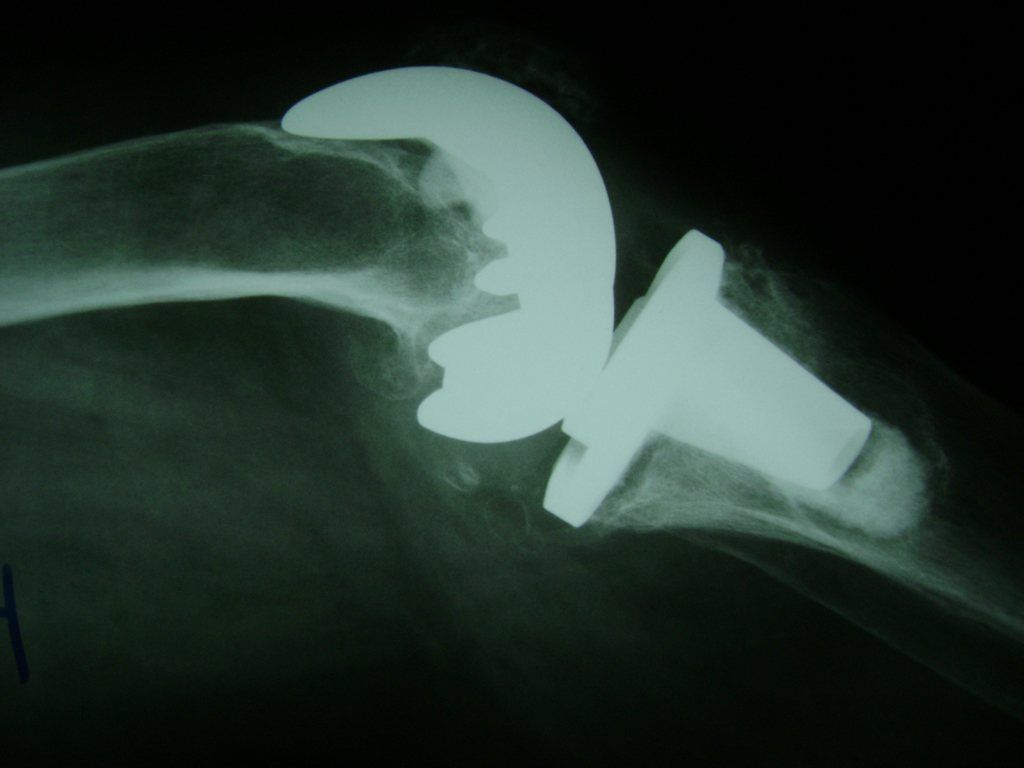

Cirugía de Fémur - Rodilla